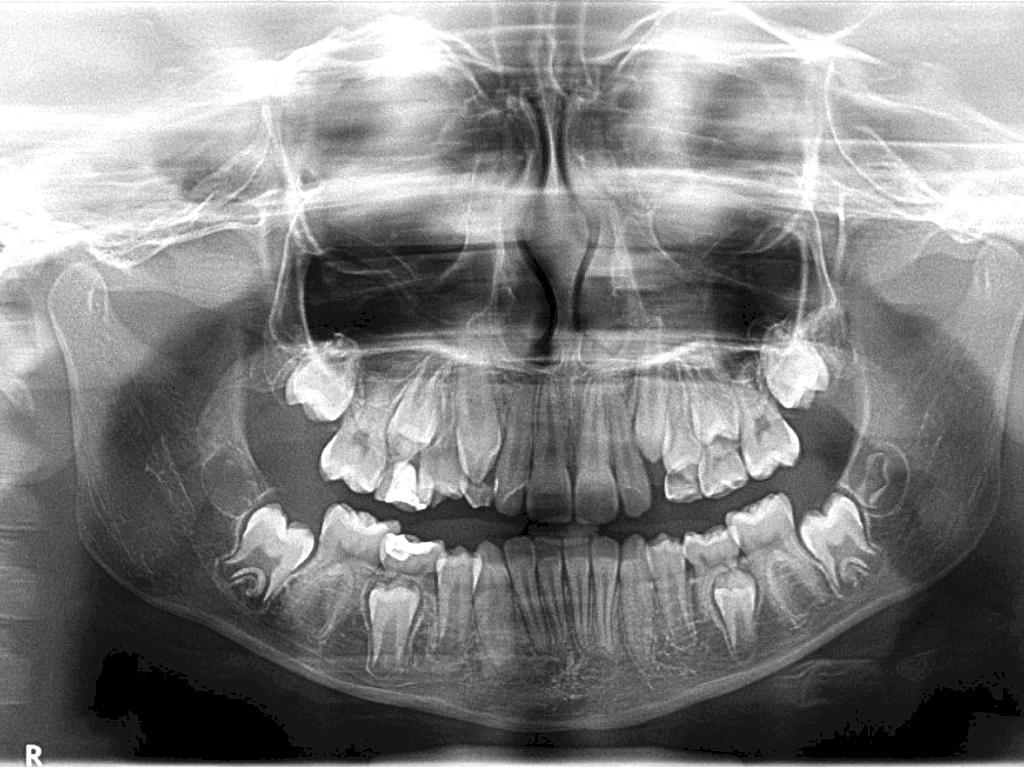

PANORAMICA

Dentición permanente completa

Sin alteraciones